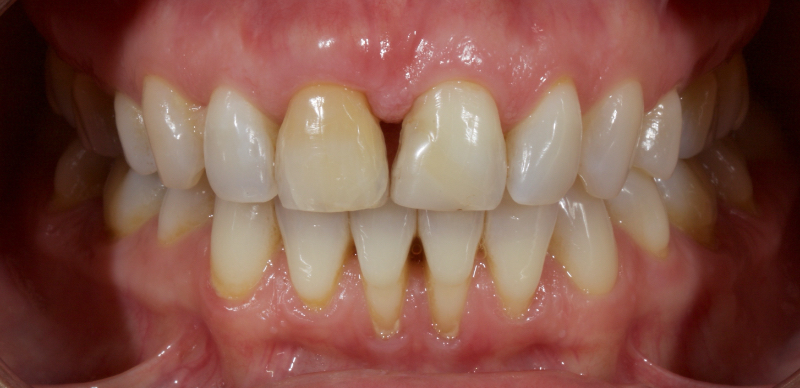

Historically, discolored anterior teeth were treated with indirect ceramic restorations, such as crowns or veneers. This can be illustrated in the case shown in Figure 1, where the discolored left central incisor (2.1), along with two other incisors, was treated with lithium disilicate ceramic veneers (Fig. 2). More recently, direct composite materials that incorporate specialized “opaquers” have also been utilized for treatment.